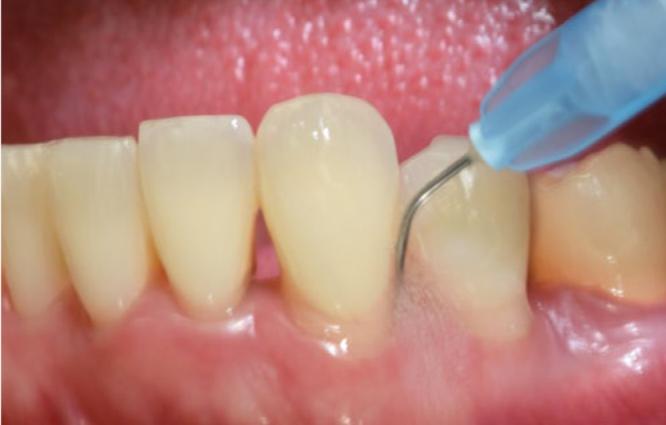

Twenty-one systemically healthy, non-smoking patients diagnosed with stage II-III, grade A/B periodontitis underwent full-mouth subgingival debridement (SD) performed with ultrasonic and hand instruments. All sites with probing depths (PD) ≥ 4 mm were treated with additional repeated (i.e., 2-3 times) instillation of sodium hypochlorite/amino acid gel in the periodontal pockets prior to and during SRP. Following mechanical debridement, a mixture of natural and cross-linked hyaluronic acid (high molecular) gel was applied in the pockets. The primary outcome variable was PD reduction; changes in clinical attachment level (CAL) and bleeding on probing (BOP) were the secondary outcomes. The clinical parameters were assessed at baseline, 3 and 6 months after therapy.

21 名系统健康、不吸烟的患者被诊断为 II-III 期、A级/B 级牙周炎,接受了全口龈下刮治术(SD),采用超声和手动器械进行。所有探诊深度(PD)≥4mm 的部位均采用额外的重复(即 2-3 次)氯酸钠/氨基酸凝胶冲洗,在 SRP 之前和期间进行。机械清创后,在牙周袋中应用天然与交联透明质酸(高分子量)凝胶混合物。主要结局变量是 PD 减少;临床附着水平(CAL)和探诊出血(BOP)的变化为次要结局。治疗后 3 个月和 6 个月评估临床参数。